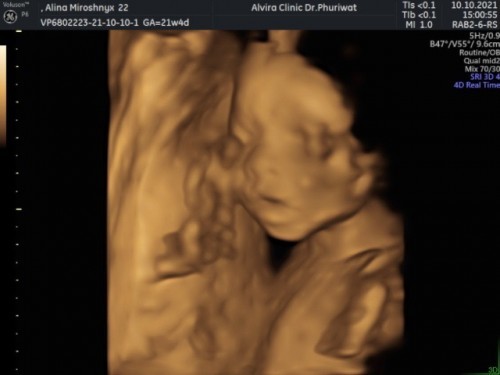

พ่อไทยแม่ยูเครน อัลตร้าซาวตอน 21 w 4 d. ครับ ตอนนี้ 28 w แล้ว อดใจรออีกไม่นานก็จะได้เจอกันแล้วครับ❤️

เห็นหน้าชัดเลยค่ะ